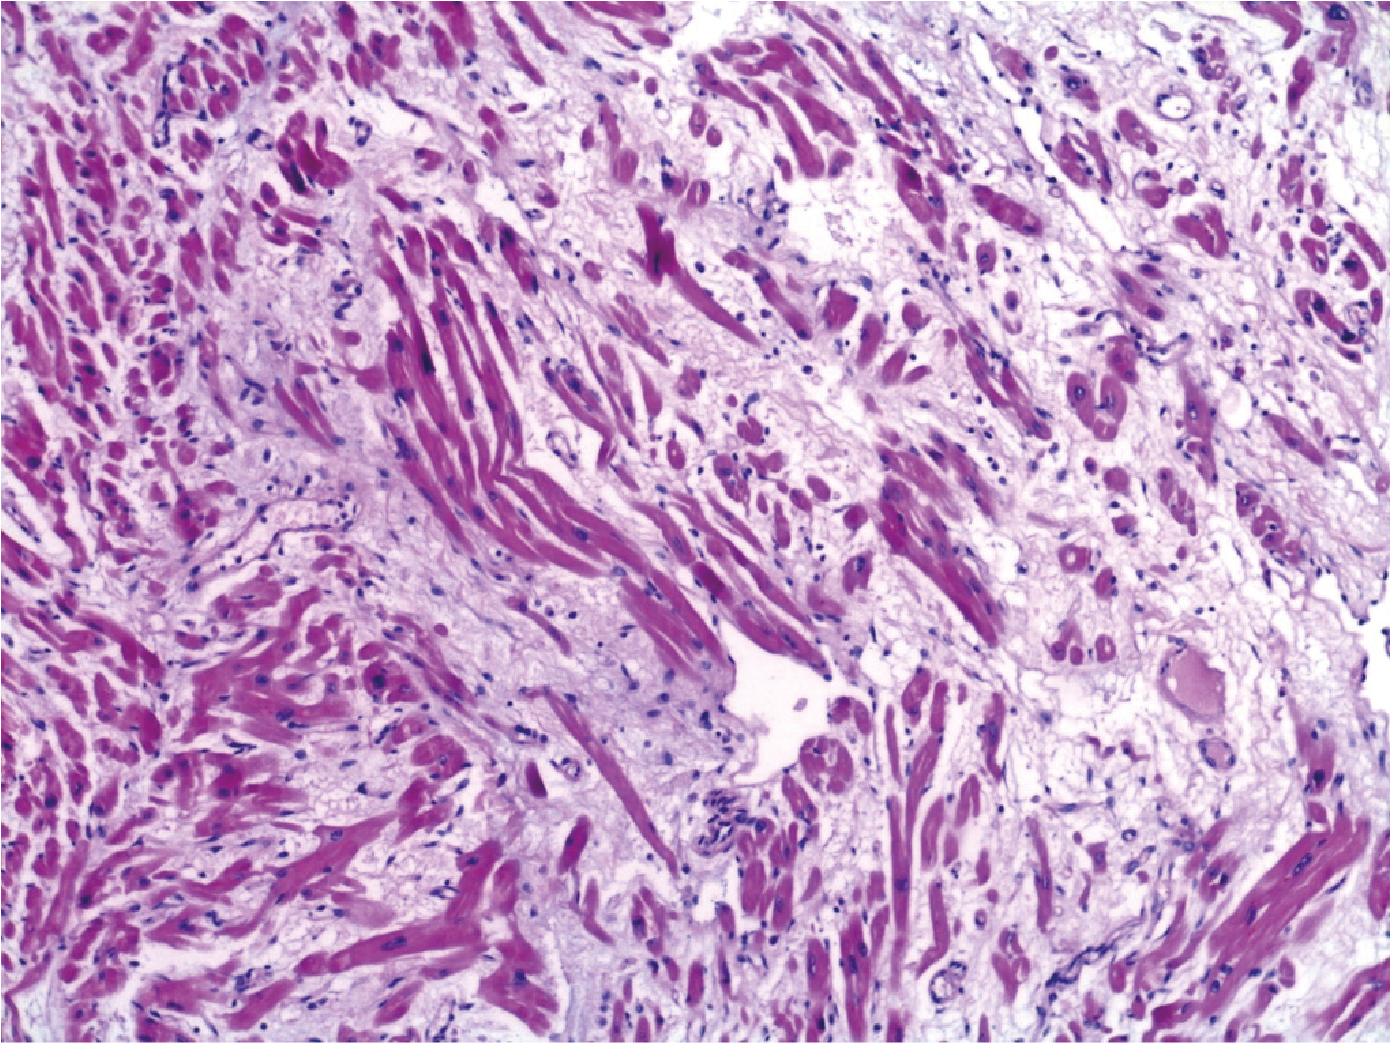

En la microscopía observamos los miocardiocitos normales con un núcleo central, y también la presencia de algunos núcleos más grandes, de bordes irregulares, y el ensanchamiento o aumento del diámetro transversal de las fibras miocárdicas. Esto es lo característico de la hipertrofia cardíaca (Fig 4). En el corte transversal se observan las mismas características, los núcleos bien globulosos. Además observamos en algunas áreas la presencia de un edema intersticial, lo cual producía la separación de las células musculares, y en algunas áreas se observa que este edema era bastante abundante (Fig 5).

En algunas áreas también se observa la presencia de un infiltrado inflamatorio y se ven células mononucleares correspondientes a linfocitos y algunas células plasmáticas. En algunas áreas este infiltrado era un poco más denso, e intenta introducirse dentro de las fibras musculares (Fig. 6A). A mayor aumento se puede observar que las células infamatorias eran de tipo mononuclear. Ante esto solicitamos técnica de inmunohistoquímica. Como dijo el doctor Estrada uno se debe ayudar con la inmunohistoquímica para diferenciar si estos infiltrados inflamatorios son fisiológicos o patológicos. Pedimos CD45 que marca las membranas de los linfocitos y se observa que son más de 14 células (Fig. 6B).

Ante esto teníamos un diagnóstico de una miocarditis. Dentro de la clasificación de Dallas era una miocarditis de tipo borderline, ya que no presentaba ni degeneración de las fibras musculares ni tampoco se observaba necrosis. Nos ayudamos con la técnica de inmunohistoquímica confirmando que tampoco era un infiltrado de tipo fisiológico. En el corte del pericardio observamos que presentaba un engrosamiento por la fibrosis. La citología del líquido pericárdico contenía células inflamatorias mononucleares con linfocitos y células plasmáticas correspondientes a una citología inflamatoria. En la macroscopía del sistema respiratorio se apreciaba una superficie externa de coloración grisáceo con puntillado negruzco que sería vinculable macroscópicamente a antracosis. Tanto el peso como las medidas se encontraban dentro de parámetros normales. En los hilios del pulmón descartamos un embolismo ya que no se observaba ningún coágulo adherido a los vasos. En el corte de la microscopía del pulmón, se apreciaba un engrosamiento de los tabiques alveolares, esto se debe al infiltrado inflamatorio mononuclear y a mayor aumento se observa la presencia de extravasación eritrocitaria y también de hemosiderofagos (Fig. 7 AB)